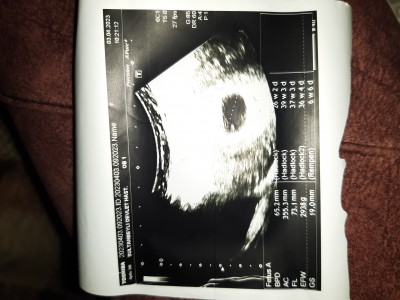

Kızlar bugün muane oldum doktor muane esnasında her şey yolunda güzel dedi ve kalp atisi dinledi bende duydum. Fakat bana kalkarken 2 hafta sonrada kalp atışı için gel dedi şimdi o dinlediği neydi yani yoksa dinlediği halde garanti olsun diye mi tekrar çağırdı.

persembe günü olan beta hcg değerim 7845 idi ben çok rahat her şey gözükür diyordum ama... resimde atıyorum değerler nasil bilen yardım edebilir mi

Gebelik haftası 6 artı 2